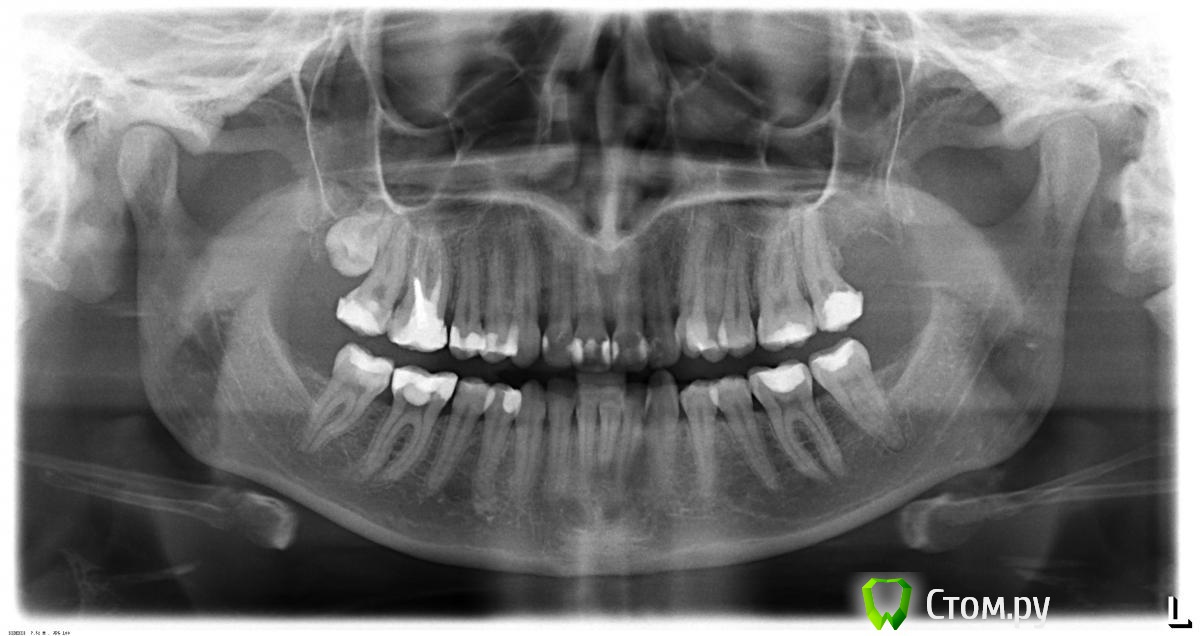

Здравствуйте! :)  Могли бы Вы  определить по снимку ..есть необходимость проводить кюретаж зубов ?

так ли необходима эта операция .. и  если все таки провести кюретаж какие зубы нужно лечить ( по нумерации )?